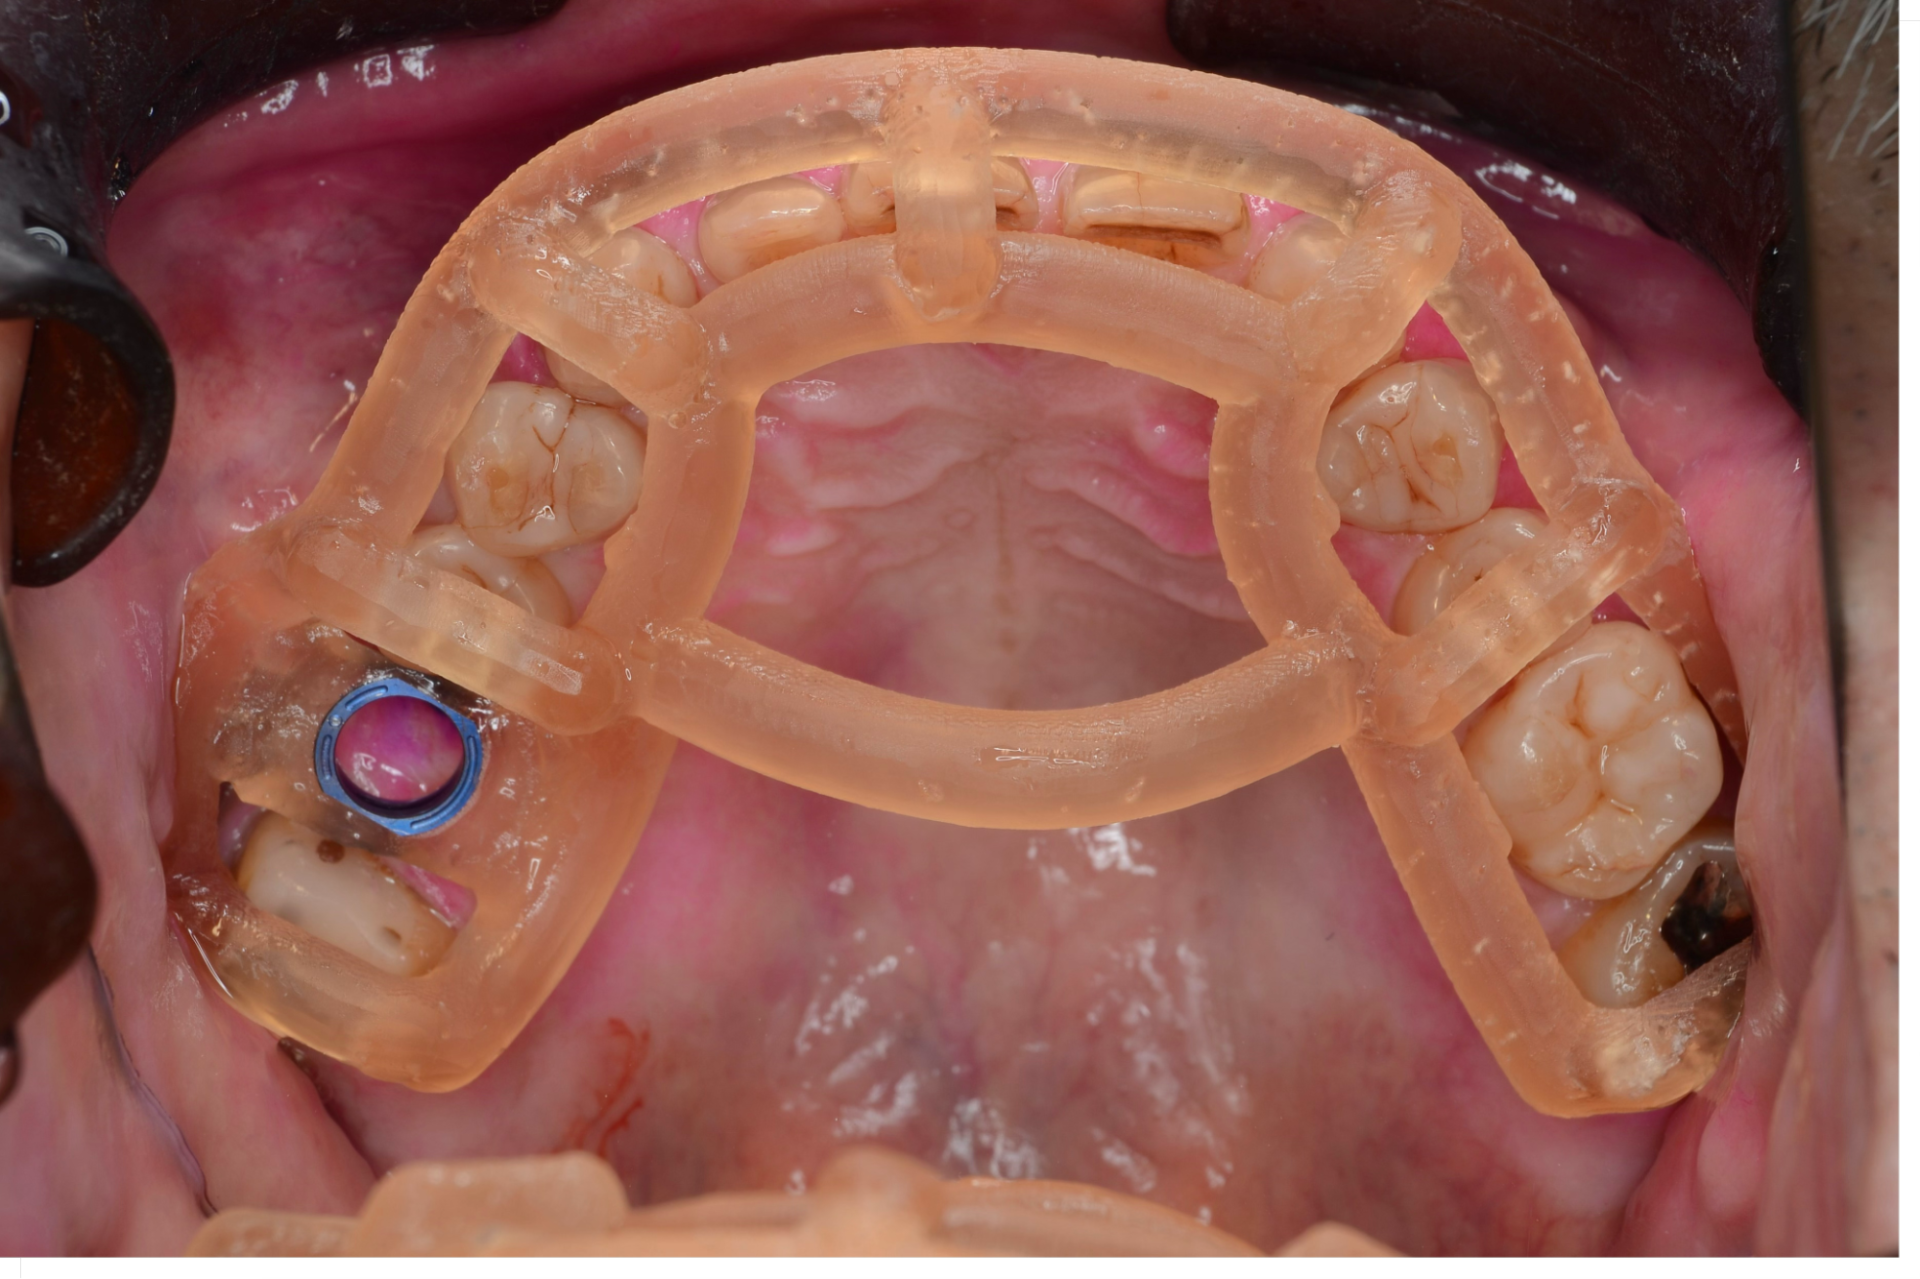

歯科技工士との打ち合わせの結果、SMOPガイドという手術用のマウスピース状の装置を作ります。ストッパー付きのドリルを使って、インプラントを入れるための穴を骨に開けていきます。ストッパー付きのドリルを使っているので、予定の深さに正確に早くインプラントを入れることができます。

SMOPガイドを装着したところ